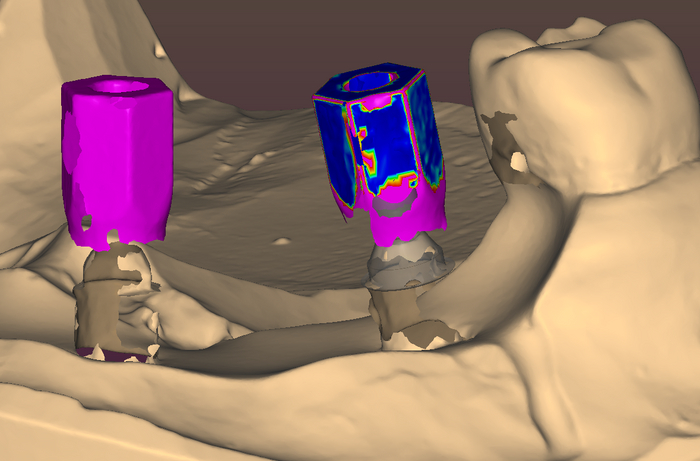

Балку получил из фрезерного центра, теперь надо её проверить на качество "посадки" на аналоги имплантов и в случае если будет баланс припассовать.

Титановый каркас "сидит" как надо не качается и не балансирует; не только на лабораторной модели, но и в полости рта — можно продолжать.